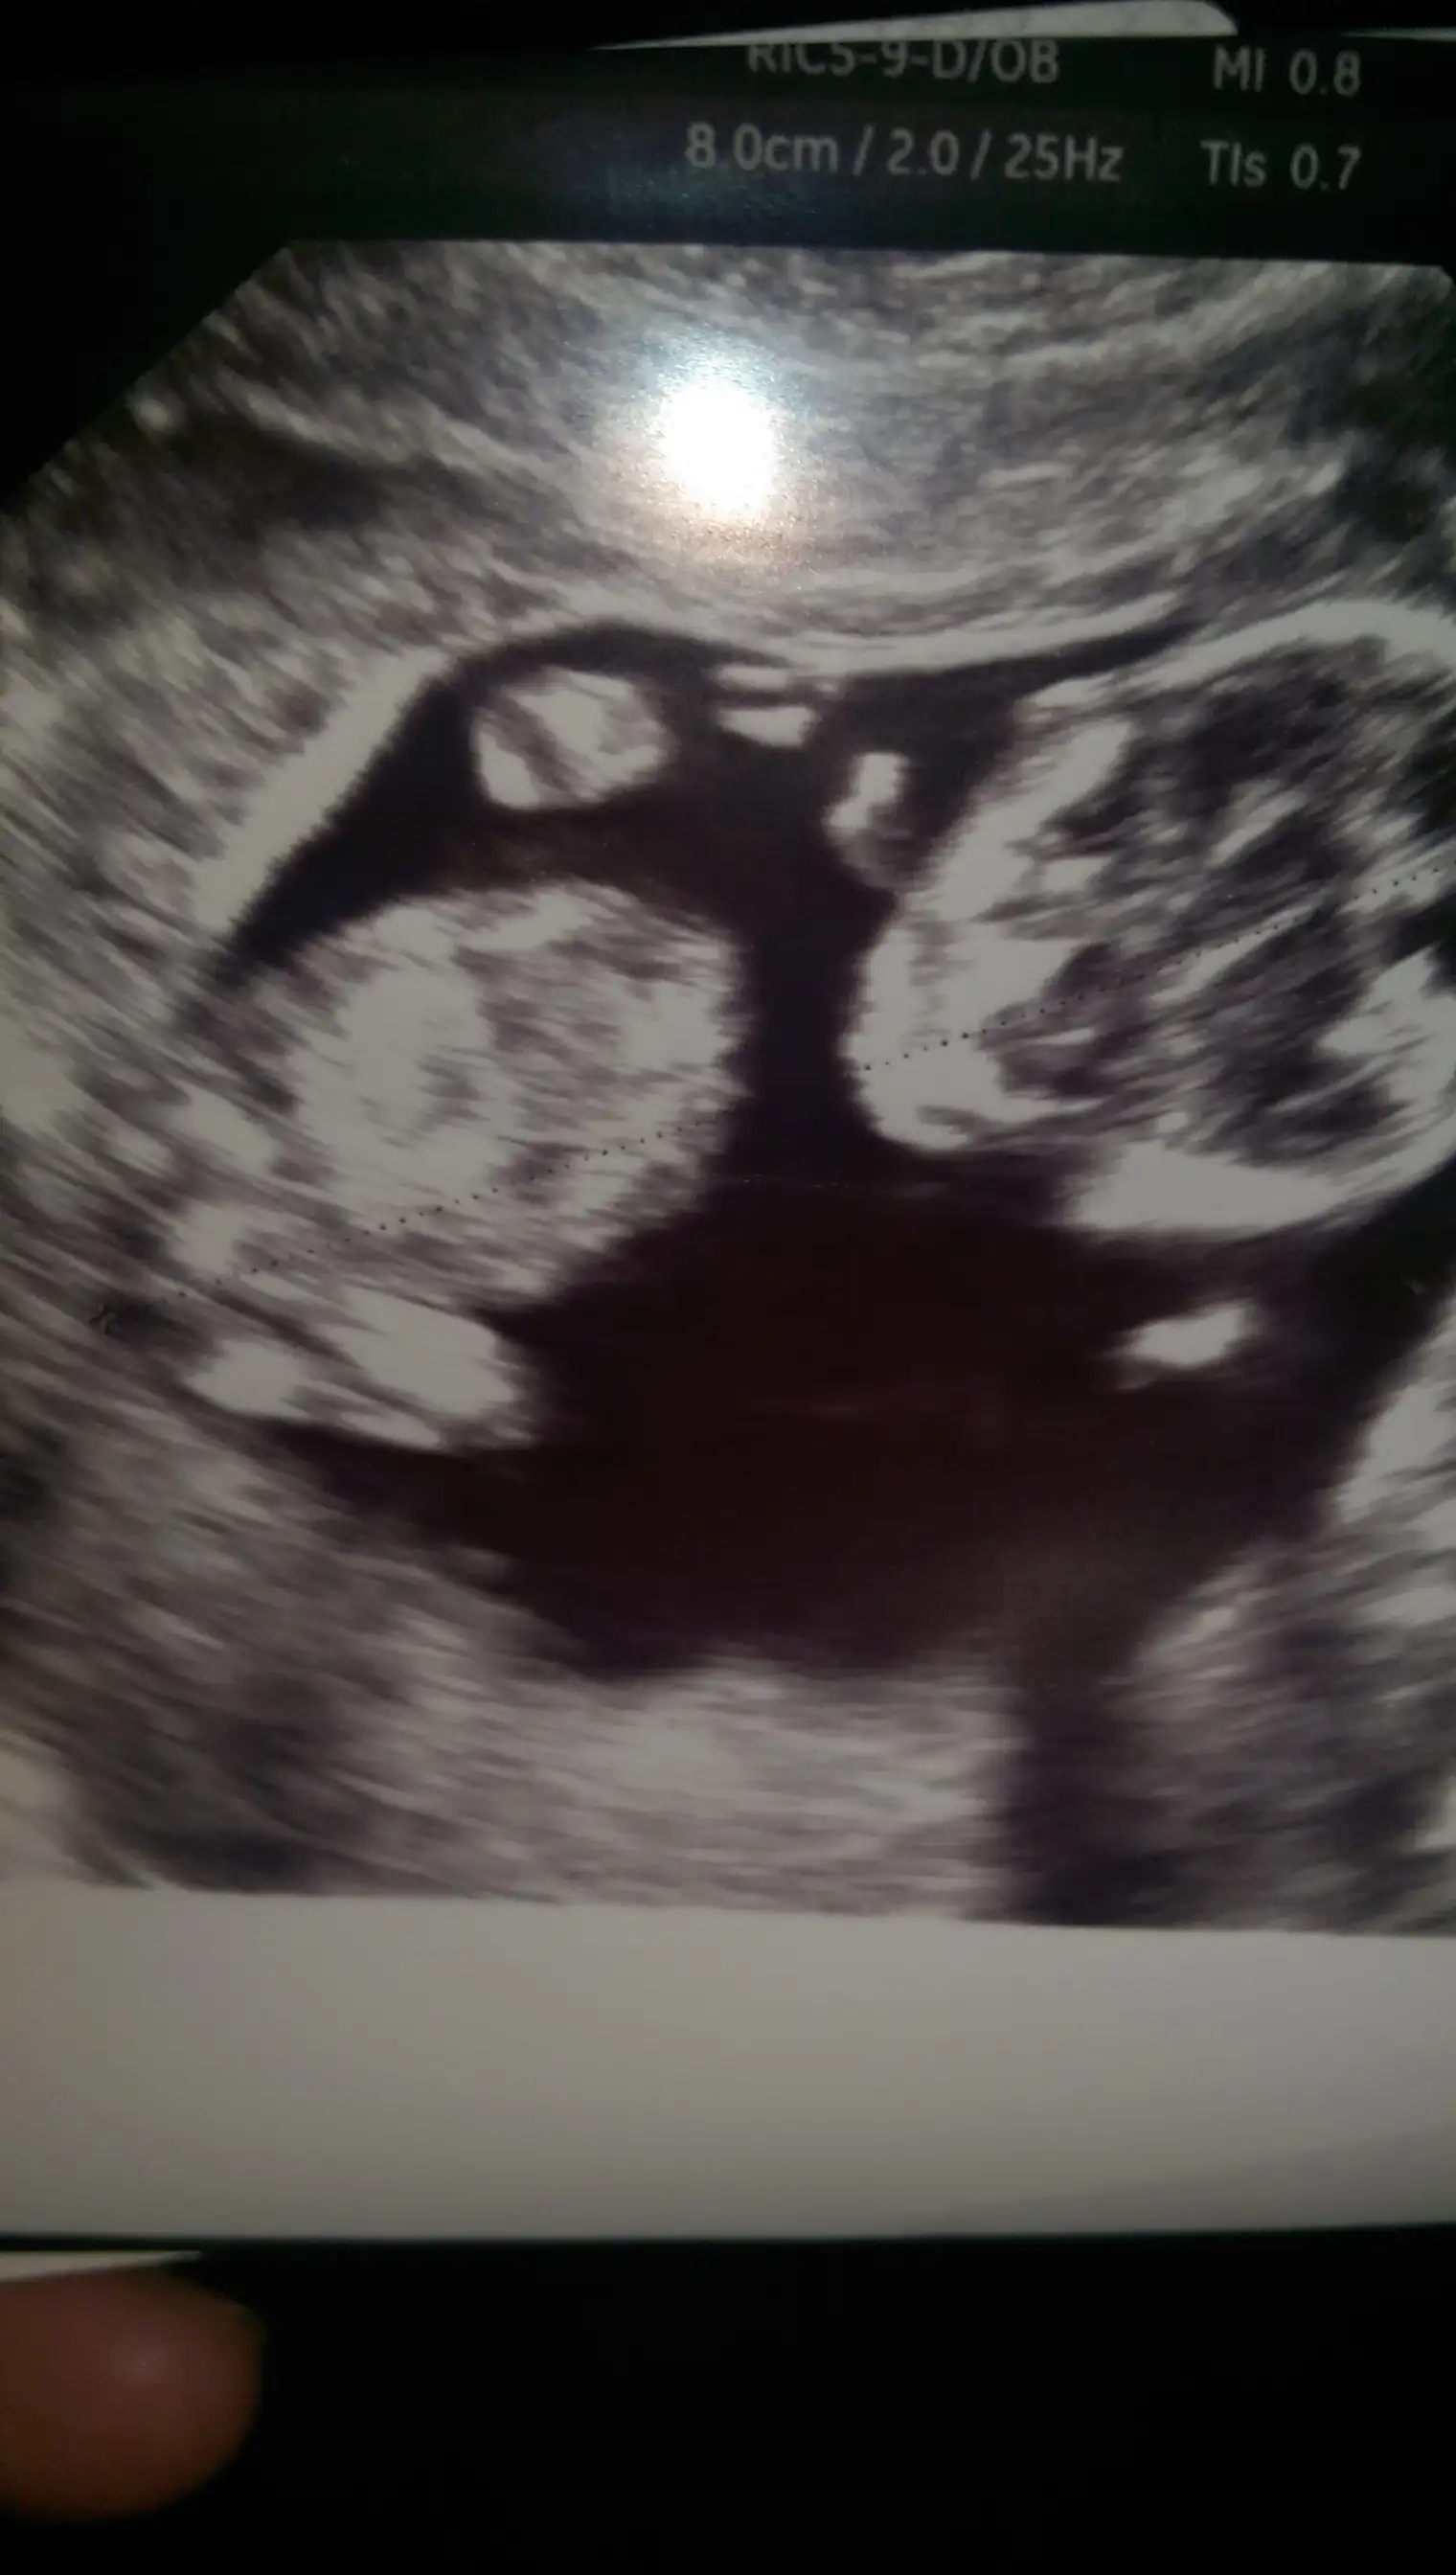

Canim esim bebisi videoya cekmisti ordan kopyaladigim bir resmi ekledim doktorun tam cikintisini isaretleyip gosterdigi yerin resmi. Onuda paylasmak istedim bi bakarsin tekrar doktorla ayni fikirdemisiniz merak ettim senin yorumunuda :anneadayı:

Ustteki fotoda erkek gibi eger kordon degilse digerlerinde kiz gibi doktor bisey dedimi